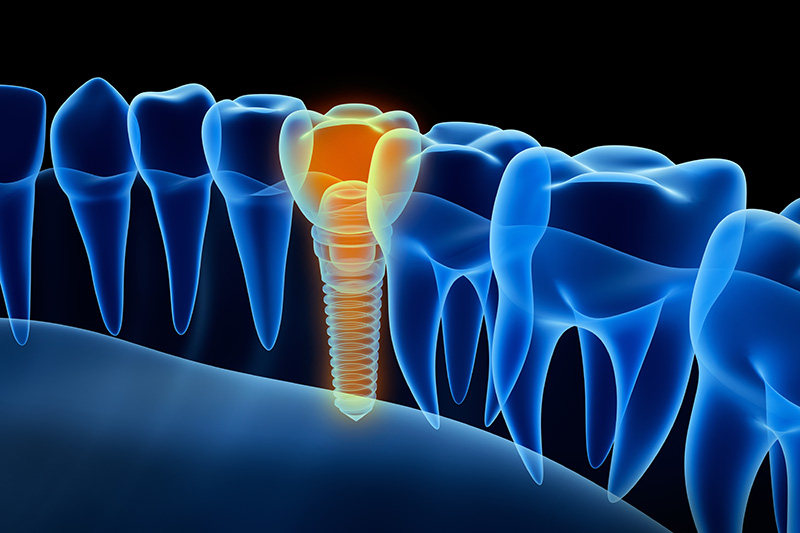

インプラント治療の実際

②インプラント埋入

インプラントが埋入された所です。POIEX HAインプラントを使用しました。大事な骨を減らさない、骨が軟らかい為、しっかりと骨の中に埋入する為、ドリルは使わず、OAMで行いました。

②インプラント埋入

インプラントを埋入したところです。位置、深さが非常に重要です。

POIEX HAインプラントを使用しました。

②インプラント埋入

抜いた部分は綺麗に掃除を行い、抜歯即時埋入、歯の無い部分はOAMにてインプラントを埋入しました。POIEX HAインプラントを使用しました。